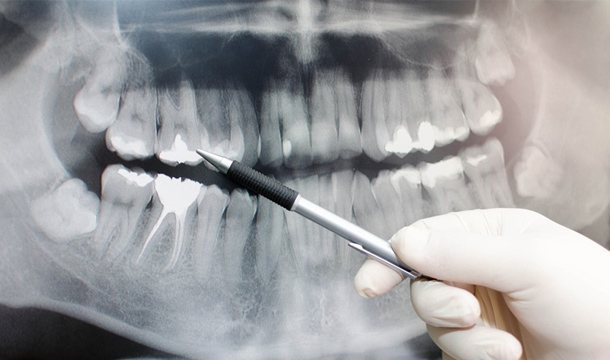

Anatomia radiculara difera foarte mult de la dintii din zona frontala, care au de regula un singur canal intr-o singura radacina, la cei din zona laterala care au de regula trei radacini si 3 sau 4 canale, putand intalni in anumite situatii anatomii atipice cu mai multe radacini sau o radacina cu mai mule canale.

De aceea taxam diferit tratamentul radicular la molari fata de incisivi, in cazul primilor tratamentul fiind mult mai dificil.